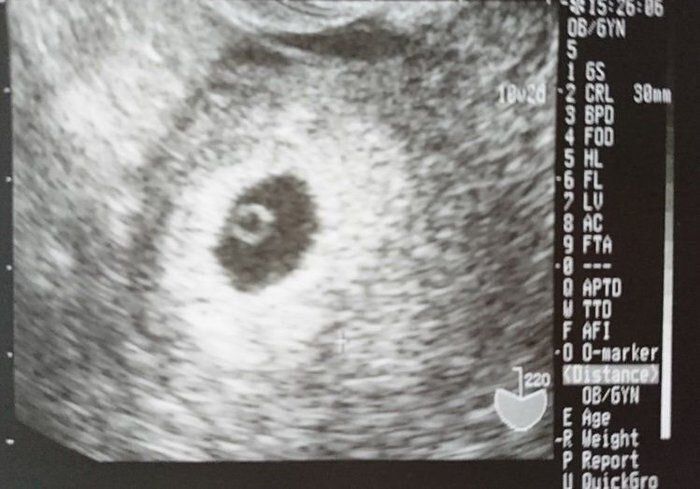

なつさんの妊娠6週目のエコー写真

妊娠発覚!2ミリくらいですと言われる。

転職活動中、「そういえば生理が来てないな。もしかして」と思い、レディースクリニックに行きました。診察してみると妊娠しており、すでに6週でした。子どもは将来いずれと思っていましたが、結婚もまだまだ先のことだと思っていたので心の準備が全くできておらず、正直ショックで「どうしよう」と思いました。呆然としながらもエコー写真を見てだんだん産みたいという決心がついてきました。